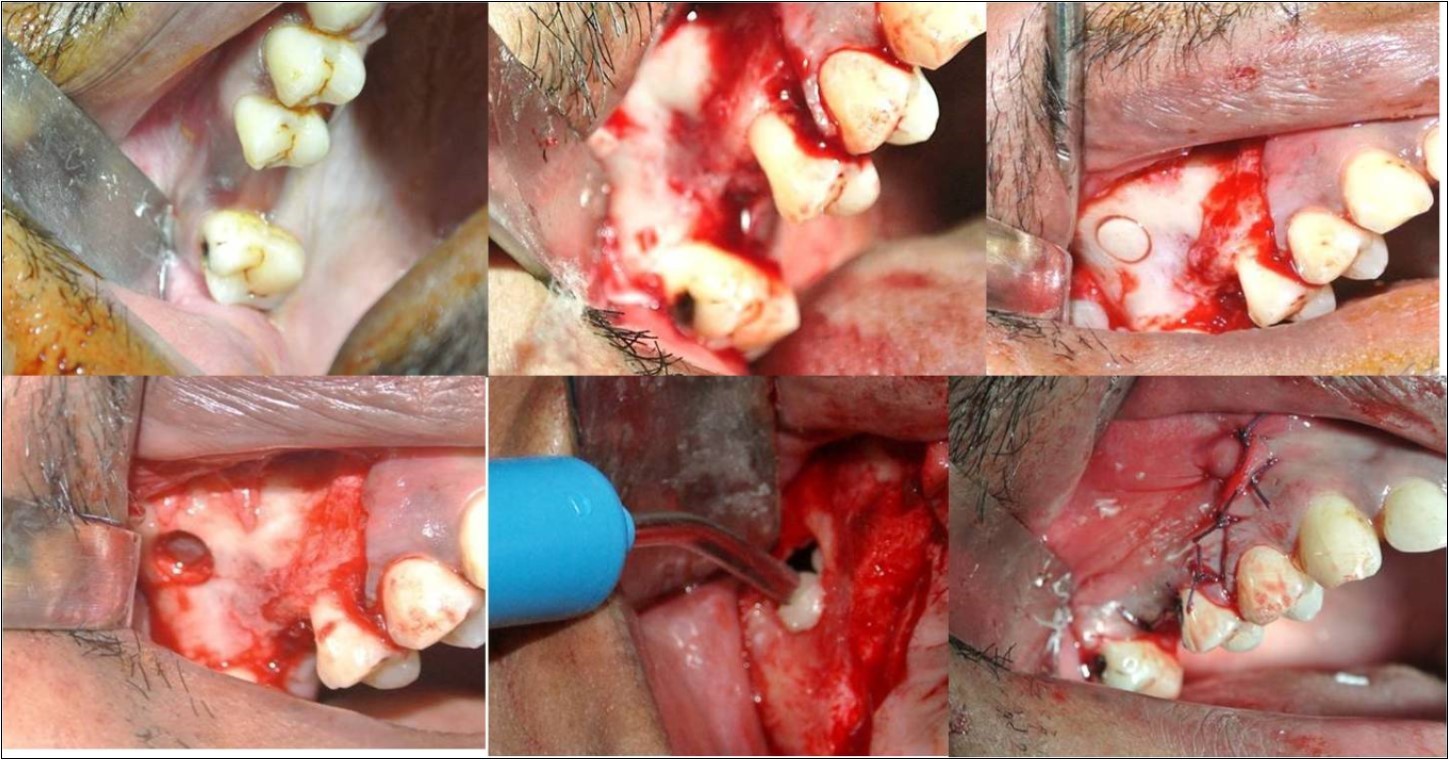

Under complete aseptic conditions, local anaesthesia with vasoconstrictor (2% lignocaine with 1:80,000 adrenaline) was used to obtain ample anaesthesia at the surgical site. Direct sinus membrane elevation was carried-out in cases with residual bone height of <5mm where a lateral spherical bone window was created using the lateral sinus approach technique. No membrane covering was used to cover the defect. (Figure 5a-f) Indirect sinus membrane elevation followed by implant placement was done in cases with residual bone height of >5mm but <9mm. (Figure 6a-h) Alloplastic graft material was then dispensed using the gun and cartridge form either through the bone window or through the crestal osteotomy site before achieving the primary closure. The patients were assessed clinically at immediate post-operative, 1 week, 1 month, 3 months and 6 months follow-up recalls post-operatively. Radiographic assessment for bone height was done pre-operatively and at 6 months follow-up recall post-operatively using Cone Beam Computer Tomography scans. In this comparative study, the measurements were tabulated and statistically analysed to evaluate the difference in increase in bone height between direct and indirect sinus augmentation procedures radiographically.

Figure 5.(a-f) Direct sinus membrane elevation carried-out under complete aseptic conditions and local anaesthesia with vasoconstrictor (2% lignocaine with 1:80,000 adrenaline) in cases with residual bone height of <5mm where a lateral spherical bone window was created using the lateral sinus approach technique; no membrane covering was used to cover the defect;